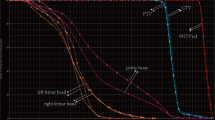

The pelvic bone marrow was defined as the contoured volumes of L4, L5, proximal femur to lesser trochanter, ilium, sacrum, ischium, and pubis using total bone as a surrogate for bone marrow, as seen in Fig. 1a. The APBM was created by first calculating the whole body mean standard uptake value (SUVwb) using the initial pretreatment PET/CT. This was done by generating a whole body contour then creating a constraint to only include the SUVs that were greater than the mean SUVwb, producing a volume defined as the constrained uptake (CU), as can be seen in Fig. 1b. The PET/CT was fused to the planning CT using MIMvista (Mimvista, Cleveland, OH) deformable registration algorithm, which was accomplished in a systematic workflow designed for this study. RegRefine was used to lock in on stable positions (sacrum and iliac crests) on the pelvis to minimize inter-patient variability in the fusion. The CU volume was transferred to the planning CT and was used to selectively isolate the bone marrow sub-volume from the PBM. The APBM volume was defined as the union of CU volume with the PBM volume (Fig. 2). The PBM and APBM volumes were collected, and the APBM/PBM fraction was calculated.